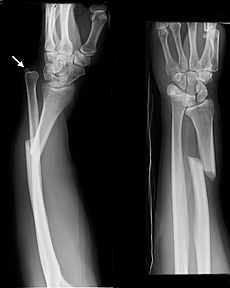

What is a Galeazzi fracture?

Fracture of the radius and dislocation of the ulna at the distal radioulnar joint

Whith any radial shaft fracture, which investigation is mandatory and why?

Lateral X-ray of the wrist

(in case of Galeazzi fracture dislocation)

How are Galeazzi fractures treated?

ORIF

A _________ fracture involves fracture of the ulnar shaft and dislocation of the proximal radial head at the elbow, whilst a __________ fracture involves a fracture of the radial shaft alongside dislocation of the ulna at the distal radio-ulnar joint

A Monteggia fracture involves fracture of the ulnar shaft and dislocation of the proximal radial head at the elbow, whilst a Galeazzi fracture involves a fracture of the radial shaft alongside dislocation of the ulna at the distal radio-ulnar join